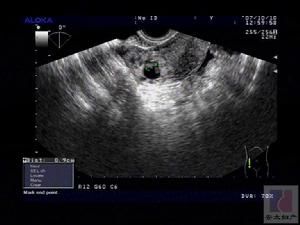

腫瘤標誌物檢查、診斷性刮宮、陰道脫落細胞檢查、腹腔鏡檢查、B超、CT等檢查等。